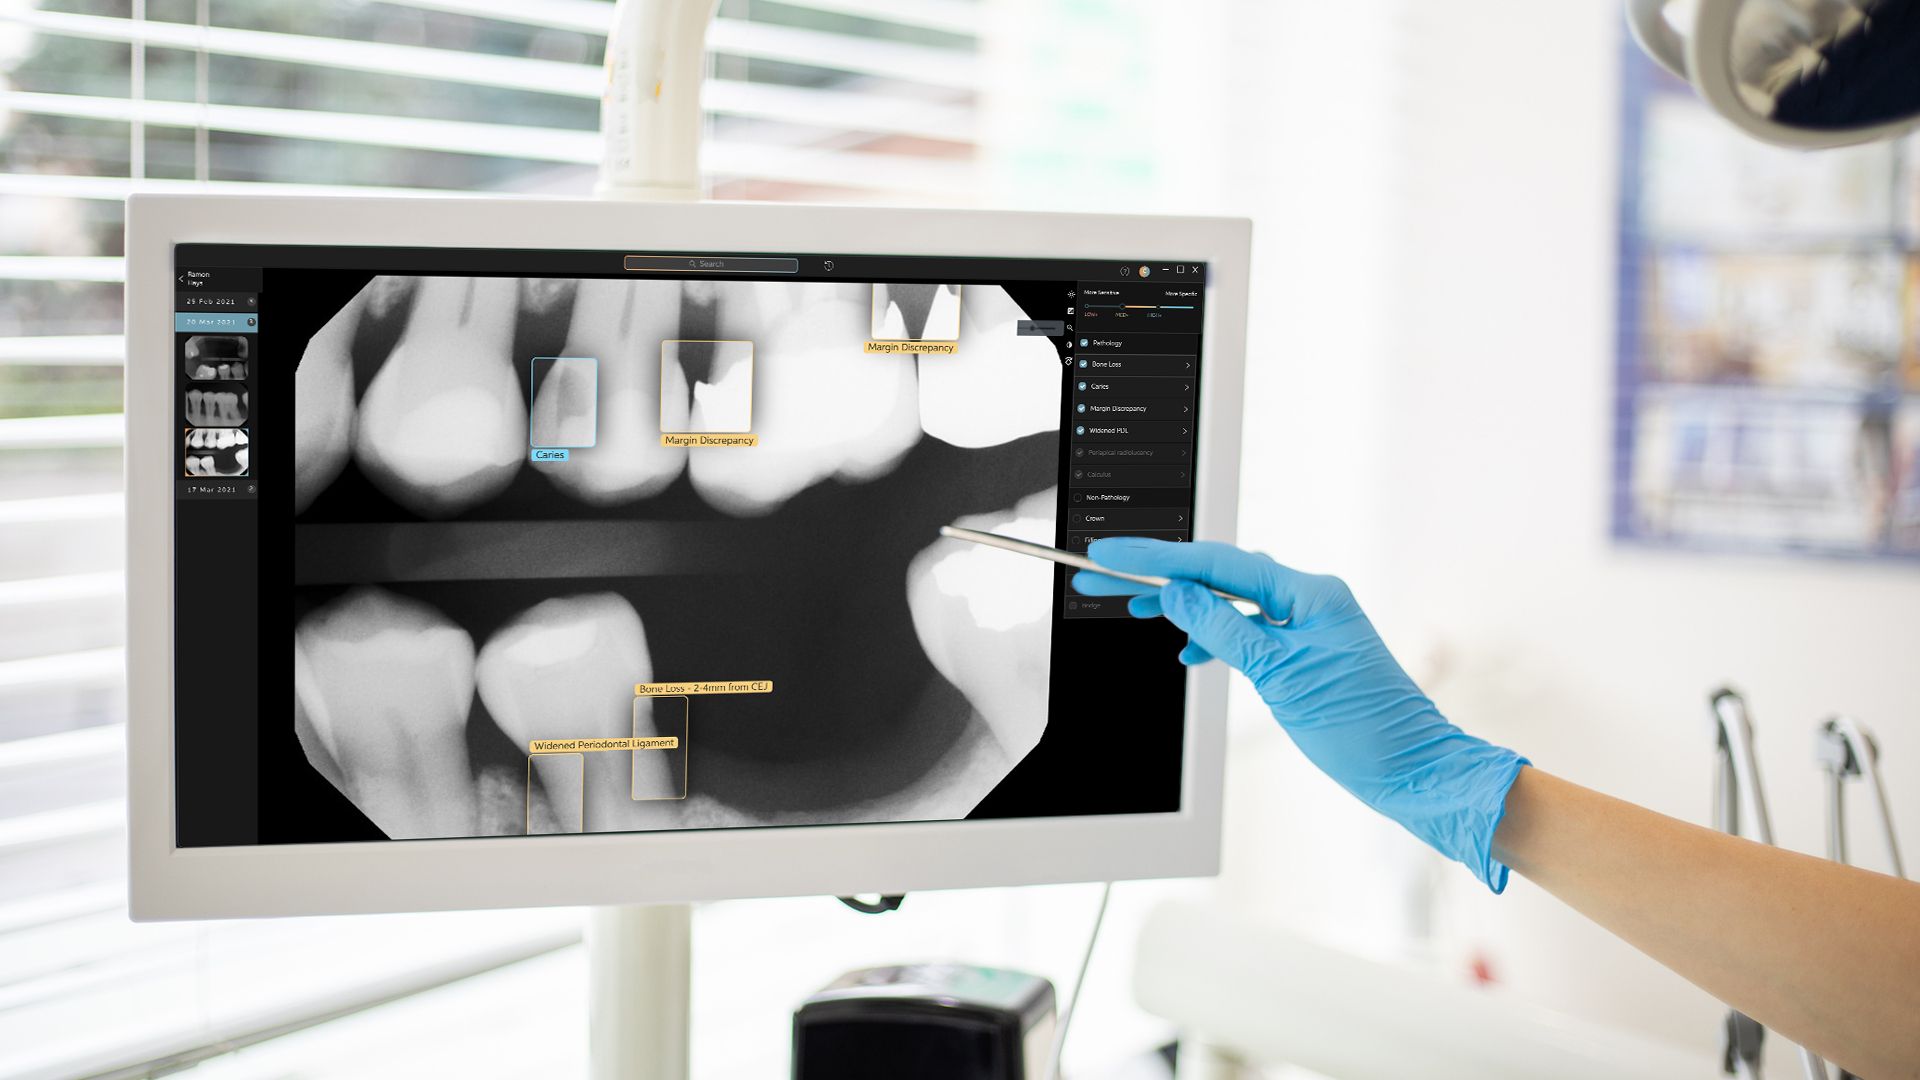

The CS 9600 features breakthrough innovations such as its artificial intelligence (AI)-powered positioning, video cameras, and Live Positioning Assistant to help enable users to produce high-quality images.

"The Swiss Army Knife of diagnostic capabilities.” – Paul Feuerstein, DMD